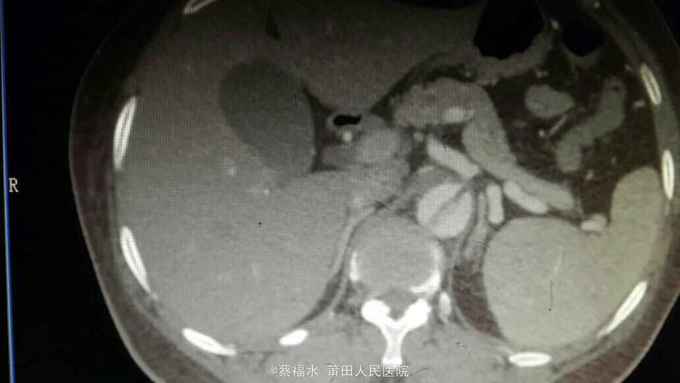

女性患者,56岁,以“上腹部、左腰部突发疼痛2小时”为主诉入院。入院查体:HR70次/分,BP220/105mmHg,双肺呼吸音清,未闻及干湿性啰音,心律齐,各瓣膜区未闻及杂音,腹平软上腹部压痛明显,无反跳痛,胆囊区无压痛,墨菲氏征阴性,肝脾肋下未及,左肾区叩痛可疑阳性,肠鸣音约5次/分。入院后查血淀粉酶正常,肌钙蛋白I阴性,心肌酶谱正常,心电图无心肌缺血改变,上腹部+胸部CT提示:右肾囊肿,余未见明显异常。予抑酸、维生素K3、曲马多等应用后,患者仍腹痛剧烈,性质同前,无明显缓解。予完善胸主动脉、腹主动脉、髂动脉CTA结果如下:

腹主动脉夹层动脉瘤 予控制血压、控制心率等治疗,患者腹痛较前缓解